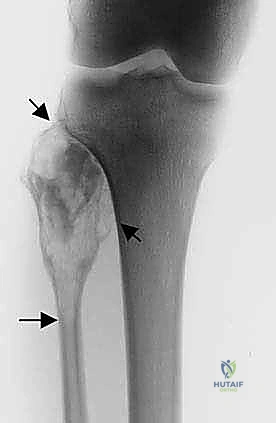

- الأشعة السينية (X-rays): الخطوة الأولى. تظهر التغيرات في الهيكل العظمي، تآكل العظم، أو التفاعلات السمحاقية (Periosteal reaction) التي تدل على وجود ورم.

* الساركوما العظمية (Osteosarcoma): الورم الخبيث الأكثر شيوعاً في العظام، وغالباً ما يصيب الأطفال والشباب. يتميز بنمو سريع وتدمير للعظم.

* ساركوما إيوينغ (Ewing Sarcoma): يصيب عادة الأطفال والمراهقين، وينشأ في تجويف النخاع العظمي للشظية.